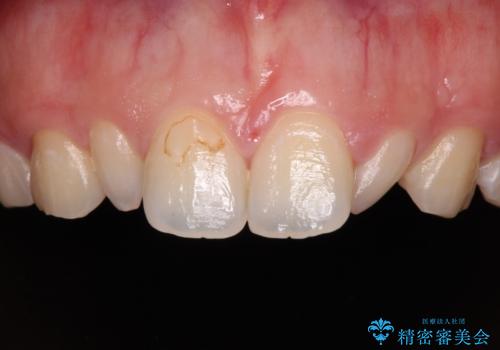

- 前歯の矮小歯と捻れや変色を気にして来院された患者様です。

結婚式が近いということもあり、前歯4本をオールセラミッククラウンにて補綴治療することとしました。